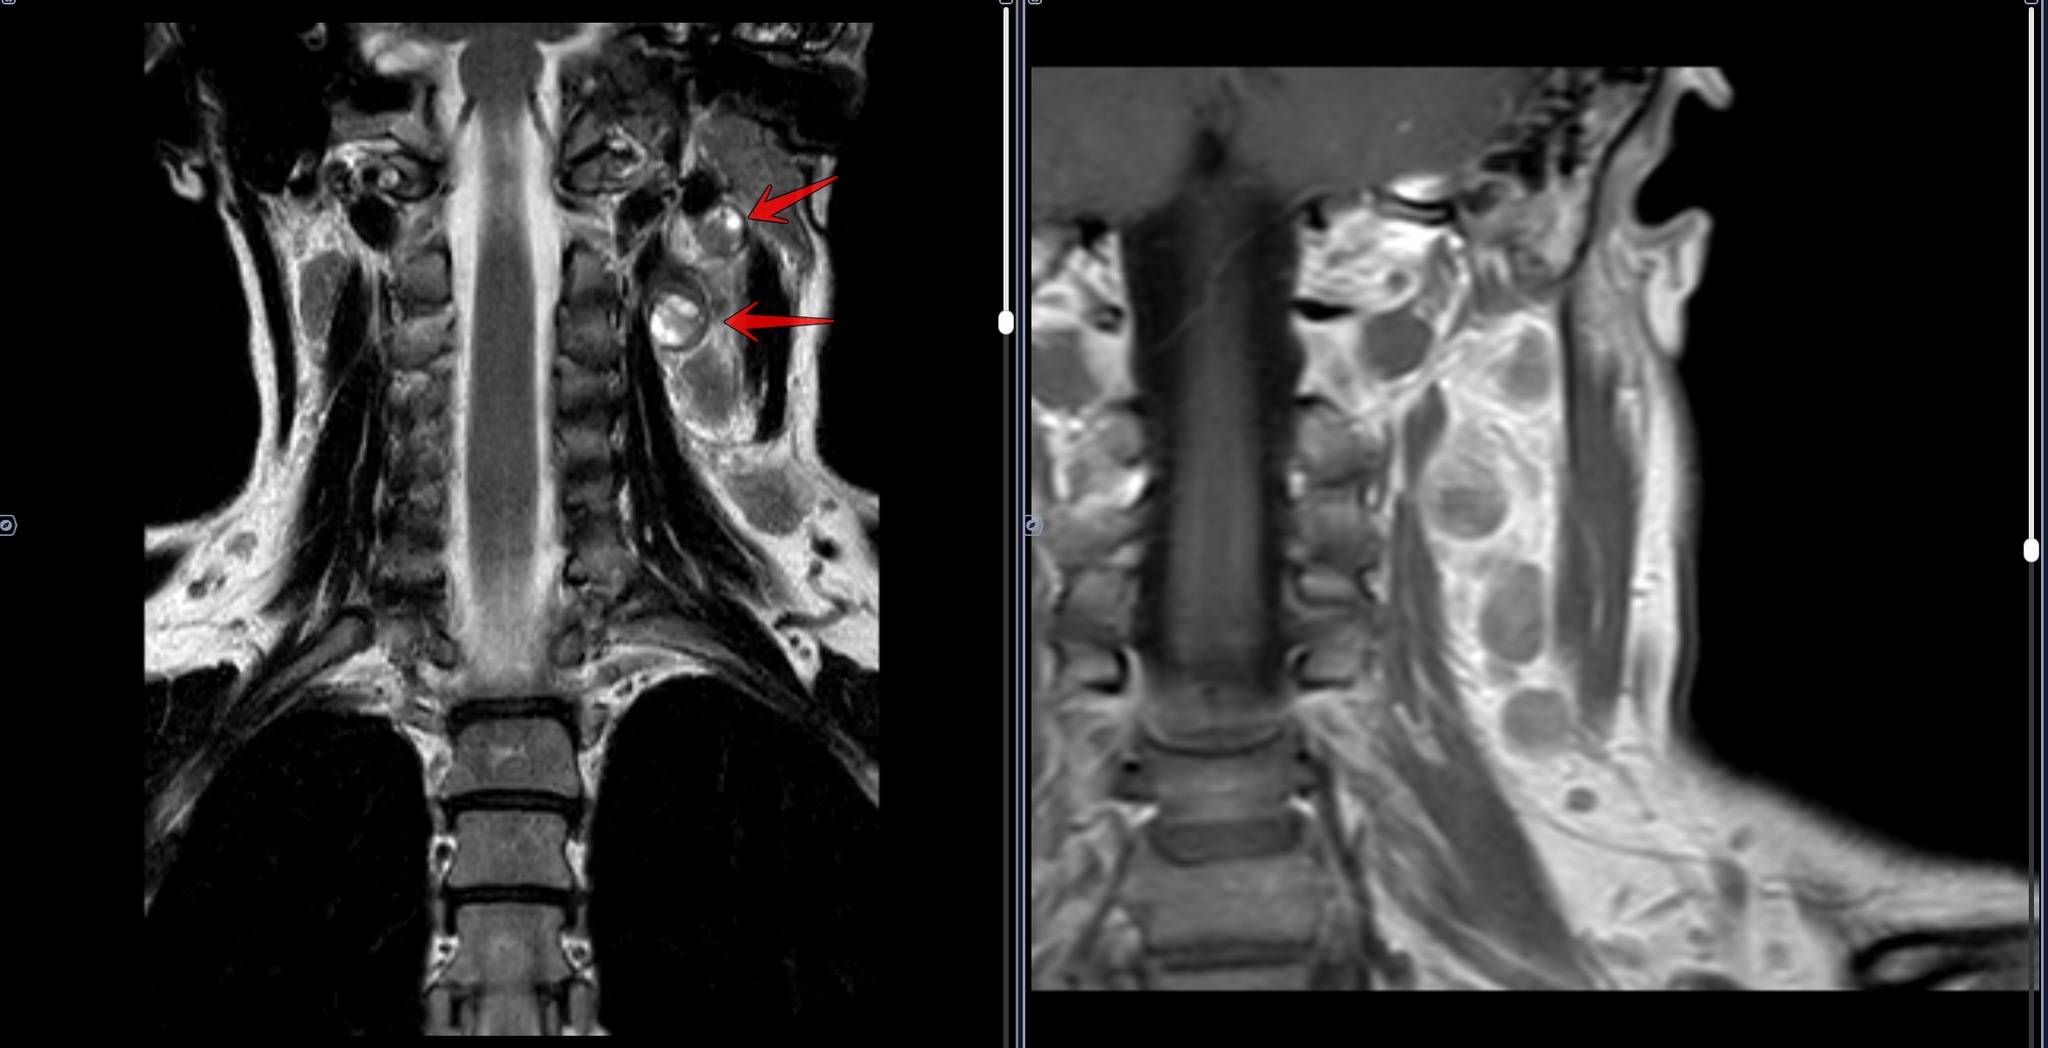

В левом окологлоточном пространстве определяется объемное образование овоидной формы, неоднородной кистозно-солидной структуры, с неоднородным контрастированием, размерами 3,4х2,4х2,3 см.

Определяются увеличенные лимфоузлы боковых поверхностей шеи неоднородной структуры, без врастания в сосуды, размерами до 1,9х1,0х2,0 см справа и до 2,9х2,4х2,4 см слева, с неоднородным контрастированием.

Заключение: МР-картина шейной лимфаденопатии - наиболее соответствует mts. Образование в левом окологлоточном пространстве: злокачественное новообразование/крупный mts в лимфоузел.